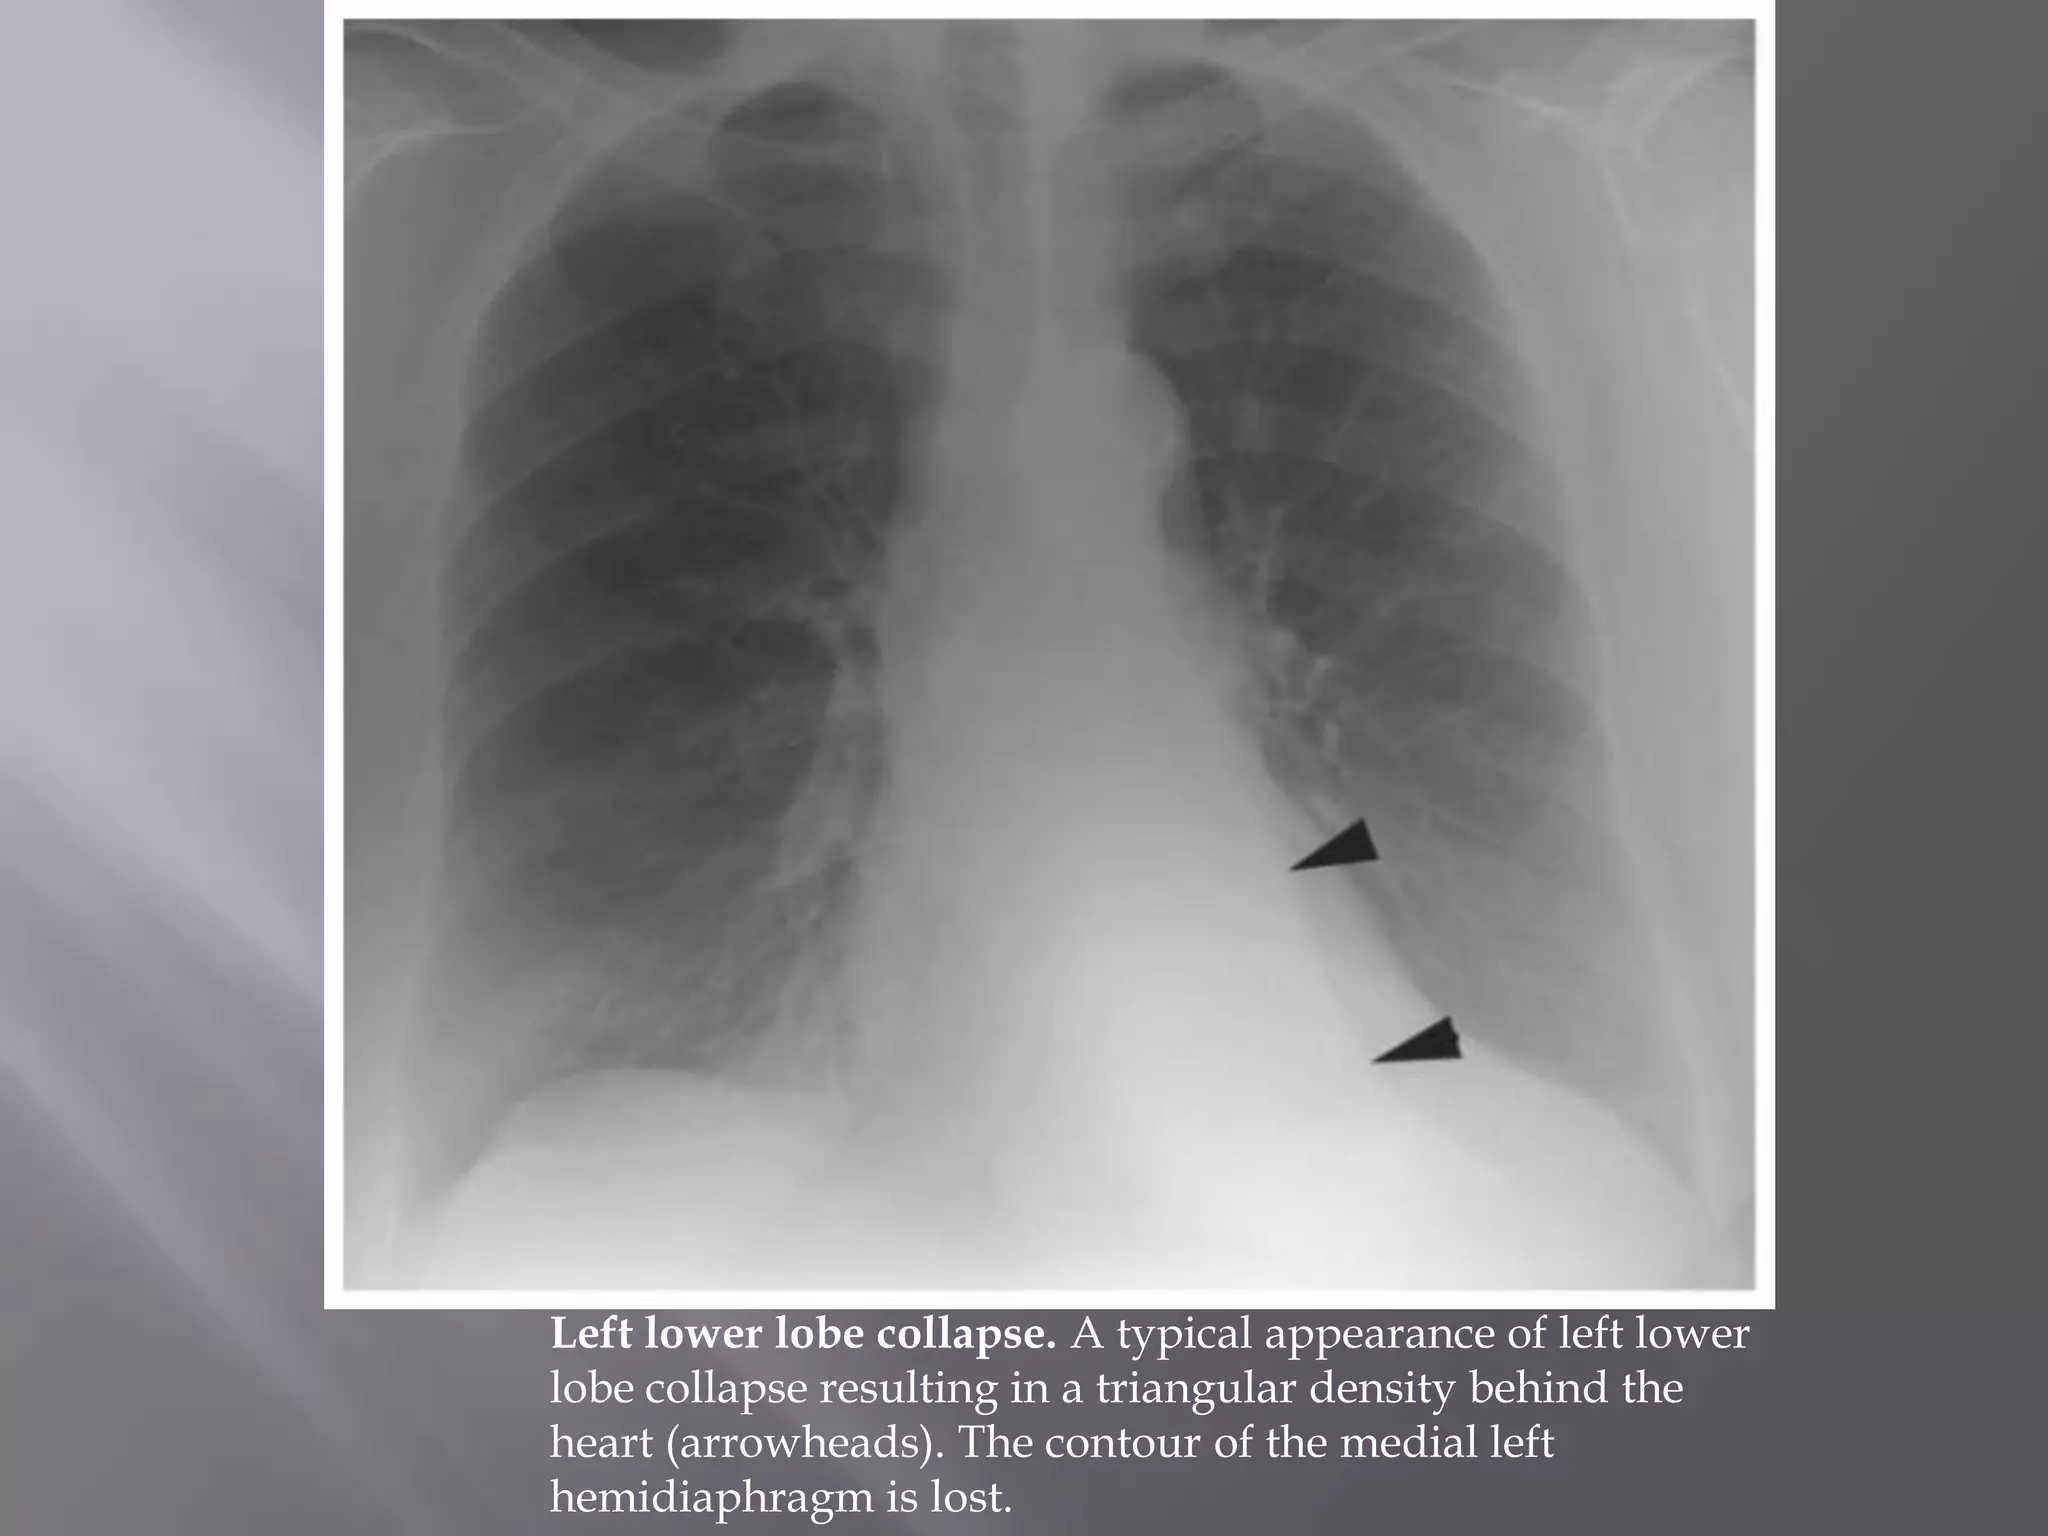

Left lower lobe collapse. A typical appearance of left lower

lobe collapse resulting in a triangular density behind the

heart (arrowheads). The contour of the medial left

hemidiaphragm is lost.

Left lower lobecollapse. A typical appearance of left lower lobe collapse resulting in a triangular density behind the heart (arrowheads). The contour of the medial left hemidiaphragm is lost.